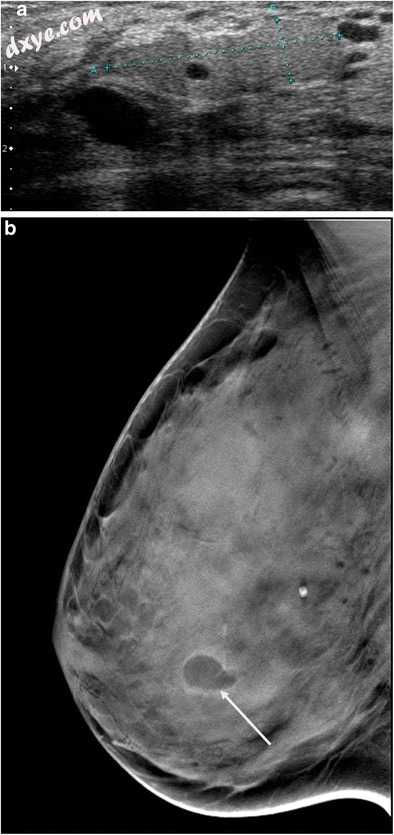

脂肪坏死

脂肪坏死是直接创伤,感染,手术或继发放疗的结果。 它可以具有可变的外观,包括巨噬细胞泡沫细胞,侧噬菌体,纤维变化或甚至钙化的区域。 在乳房X线照相术中,脂肪坏死可能表现为射线可透过的囊肿,可能与厚钙化有关,质量或扭曲有毛刺或不规则边缘。 超声波外观是可变的,有时是高回声,单纯性囊肿,或包含固体和囊性成分的复杂肿块(图3a)[9]。 可以通过提示性临床设置和乳房X线照相术中脂肪密度含量的证明来确定诊断(图33b)。

图3

脂肪坏死。 超声扫描显示由无回声脂肪成分(星号)和回声纤维成分(箭头)组成的复杂质量。 b乳房X线摄影,斜视图,显示投射在夹子上的射线可透射形成